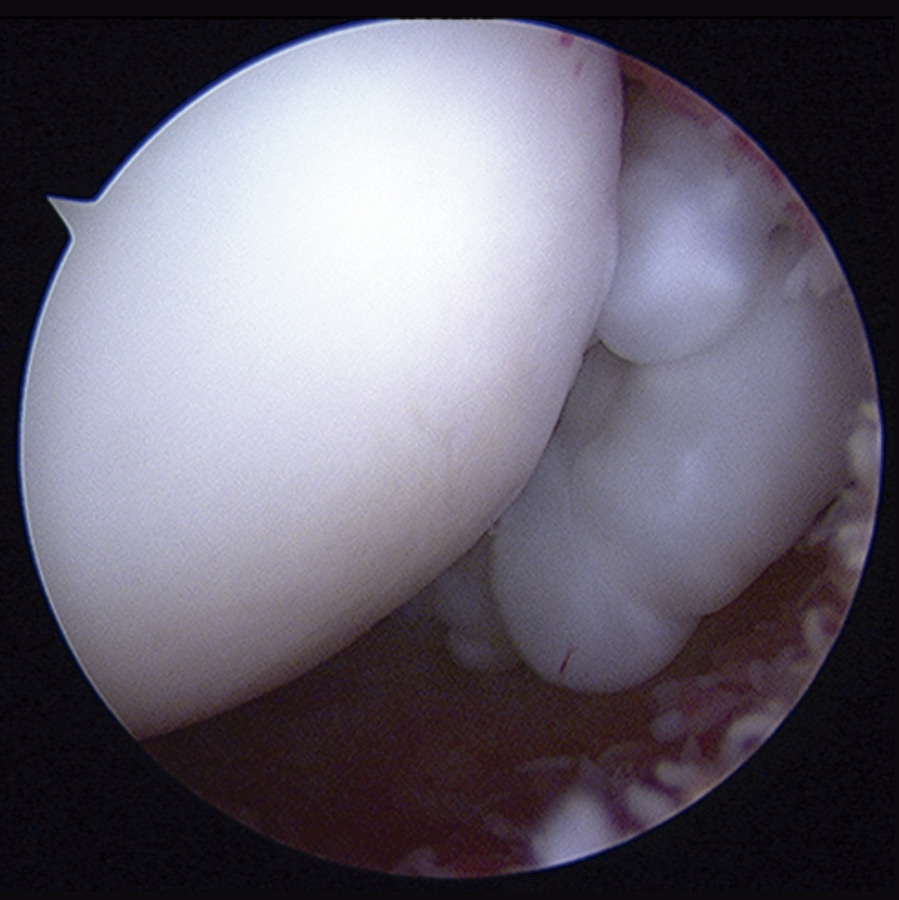

Con el diagnóstico de condromatosis sinovial de hombro derecho se procedió a la realización de una artroscopia, viendo múltiples cuerpos libres intraarticulares, la mayoría de ellos de consistencia cartilaginosa (Figuras 3 y 4) y se procedió a su extracción por vía artroscópica (Figura 5). Tras la cirugía, se remitió a la paciente a recuperación funcional, presentando una buena evolución clínica. La paciente se encuentra asintomática en el momento actual, presentando un balance articular completo.

Figura 4. Imagen artroscópica: cuerpos libres en condromatosis sinovial.